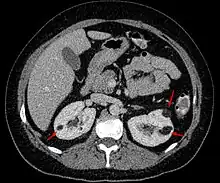

| Angiomyolipoma in both kidneys (arrows) in computer tomography. The tumours are hypodense (dark) due to fat content. | |

Angiomyolipomas are strongly associated with the genetic disease tuberous sclerosis, in which most individuals have several angiomyolipomas affecting both kidneys. They are also commonly found in women with the rare lung disease lymphangioleiomyomatosis. Angiomyolipomas are less commonly found in the liver and rarely in other organs. Whether associated with these diseases or sporadic, angiomyolipomas are caused by mutations in either the TSC1 or TSC2 genes, which govern cell growth and proliferation. They are composed of blood vessels, smooth muscle cells, and fat cells.

Three methods of scanning can detect angiomyolipomas: ultrasound, computed tomography (CT), and magnetic resonance imaging (MRI).[5] Ultrasound is standard and is particularly sensitive to the fat in angiomyolipomas, but less so to the solid components. However, accurate measurements are hard to make with ultrasound, particularly if the angiomyolipoma is near the surface of the kidney (grade III).[4] CT is very detailed and fast, and allows accurate measurement. However, it exposes the patient to radiation and the dangers that a contrast dye used to aid the scanning may itself harm the kidneys. MRI is safer than CT, but many patients (particularly those with the learning difficulties or behavioural problems found in tuberous sclerosis) require sedation or general anaesthesia, and the scan cannot be performed quickly.[3] Some other kidney tumours contain fat, so the presence of fat is not diagnostic. Distinguishing a fat-poor angiomyolipoma from a renal cell carcinoma (RCC) can be difficult.[6] Both minimal fat AMLs and 80% of the clear-cell type of RCCs display signal drop on an out-of-phase MRI sequence compared to in-phase.[7] Thus, a lesion growing at greater than 5 mm per year may warrant a biopsy for diagnosis.[3]